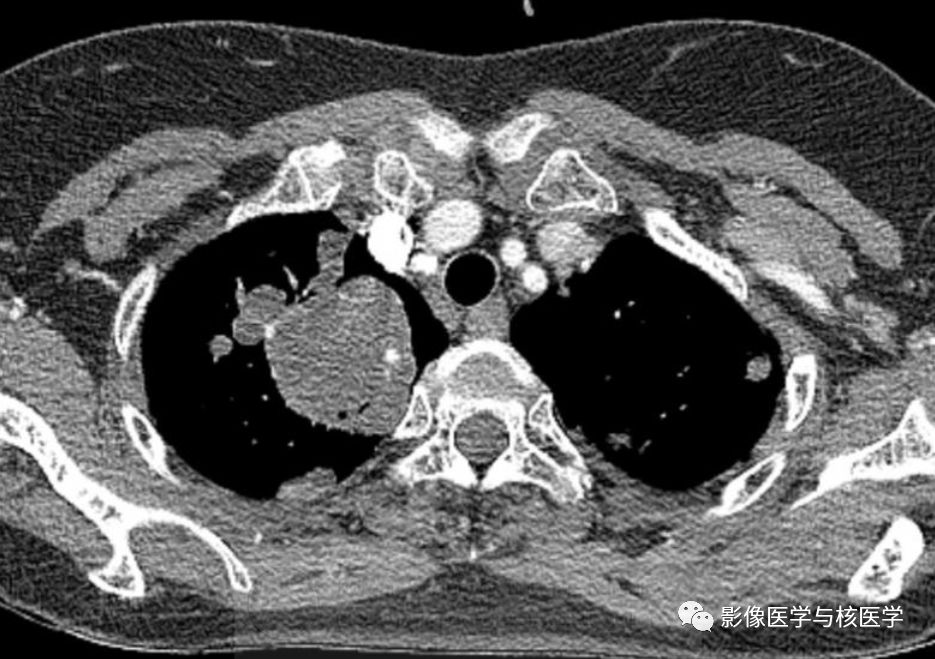

图4 胸部CT增强

Figure 2-4. On chest CT after chest tube insertion in left hemithorax, there are multiple nodules and masses with/without cavity in both lungs.

图2-4.胸部CT显示左侧气胸置管后,两肺多发结节或肿块伴或不伴空洞。